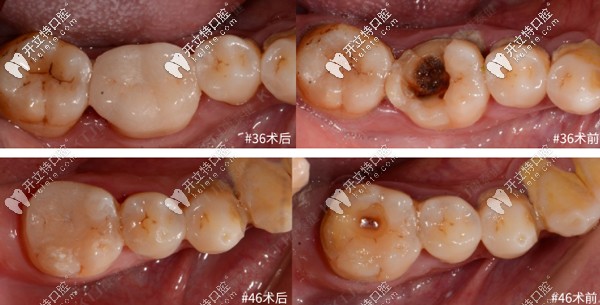

修復(fù)前后對(duì)比如下:

瓷嵌體修復(fù)前后對(duì)比